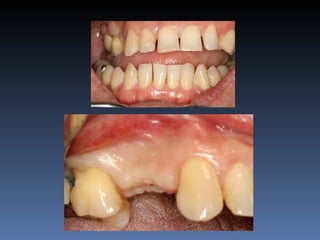

BOX 1

Diagnóstico: Desdentada total maxila

BOX 1 Maura GraçaMontereiro Idade – 59 anos Sexo – Feminino Raça – Caucasiana ASA – II Data- 27-04-2012 Diagnóstico: Desdentada total maxila já reabilitada com “All-on-four” híbrido; periimplantite dos implantes anteriores. Plano de tratamento: Remoção dos implantes anteriores, instalação de dois implantes Zigomáticos e dois implantes posteriores na tuberosidade.